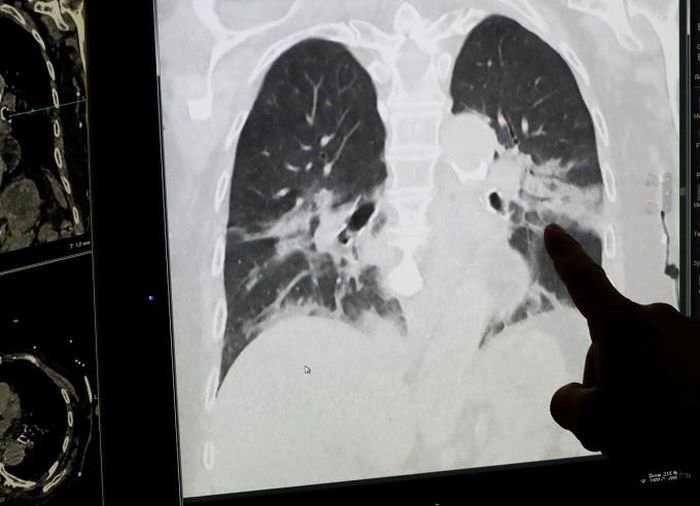

Hình chụp X-quang phổi của một bệnh nhân Covid-19 tại Bệnh viện Trung tâm CHR tại Liege, Bỉ, ngày 22/4/2020. Ảnh: Reuters